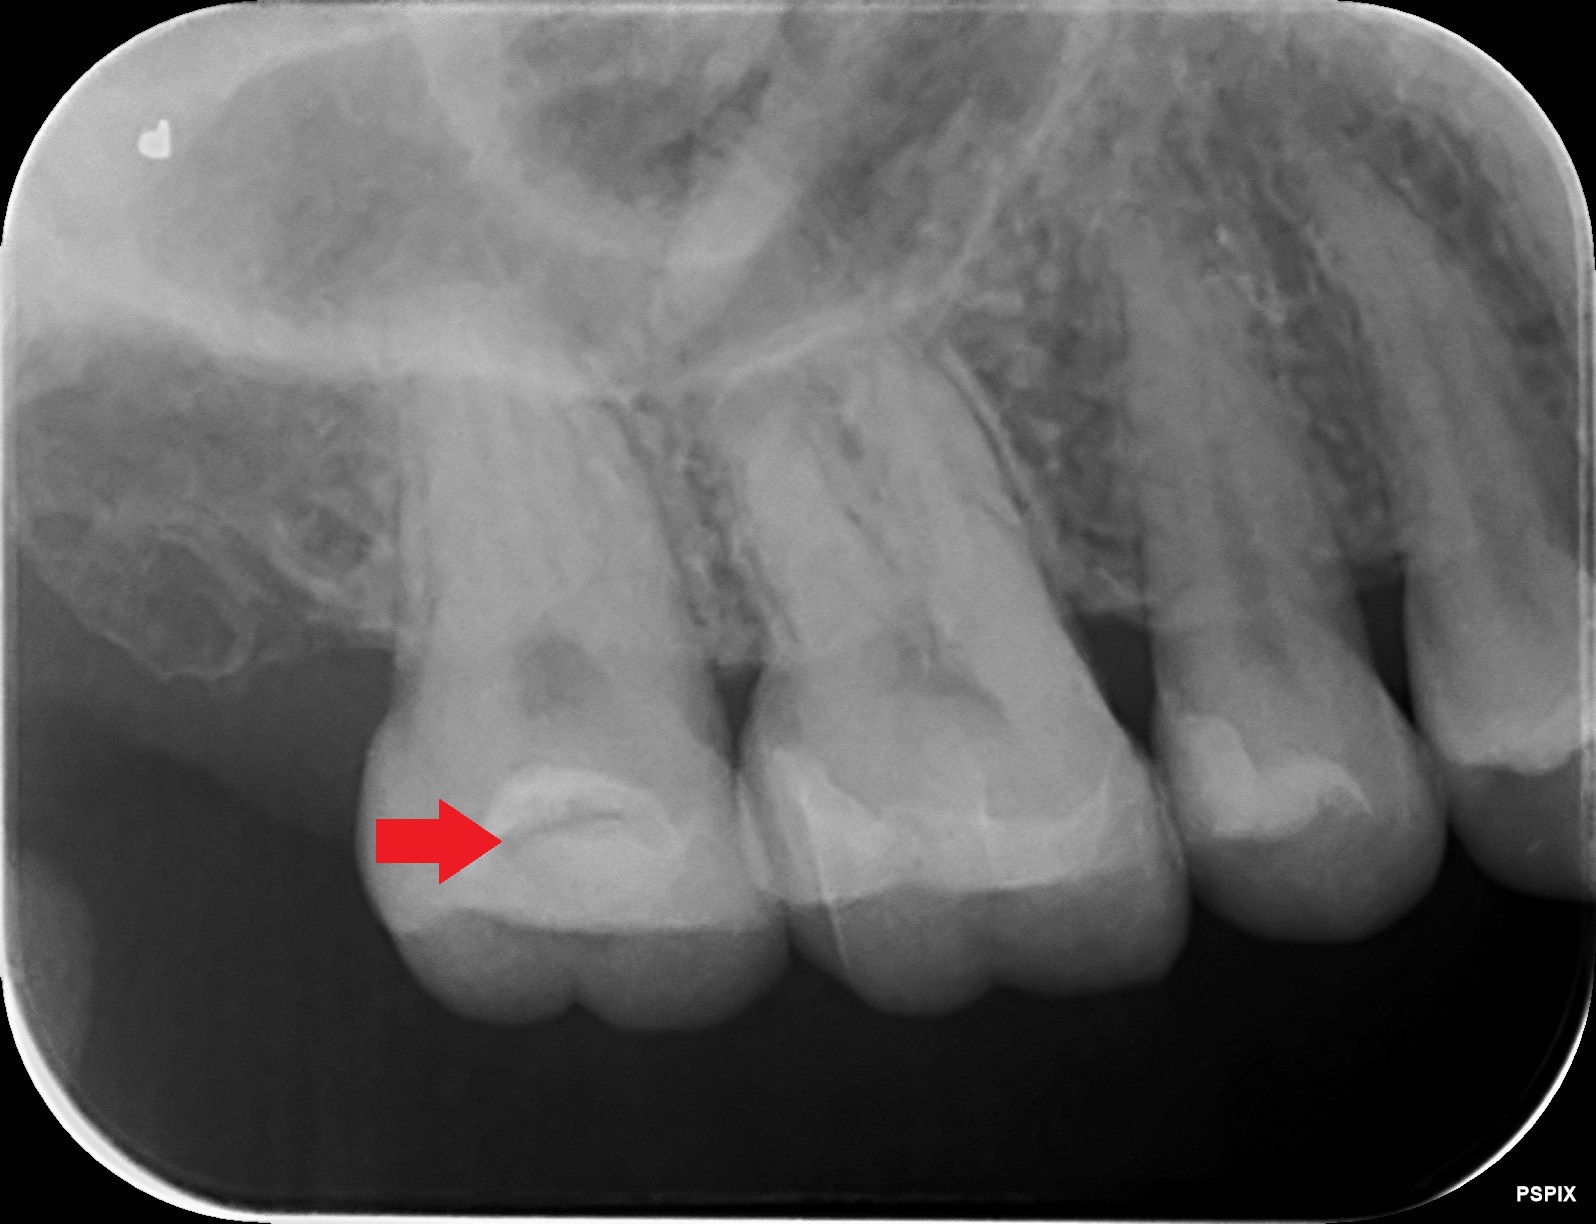

ゴールドインレー(金合金)が虫歯?その原因は?

• Before

After